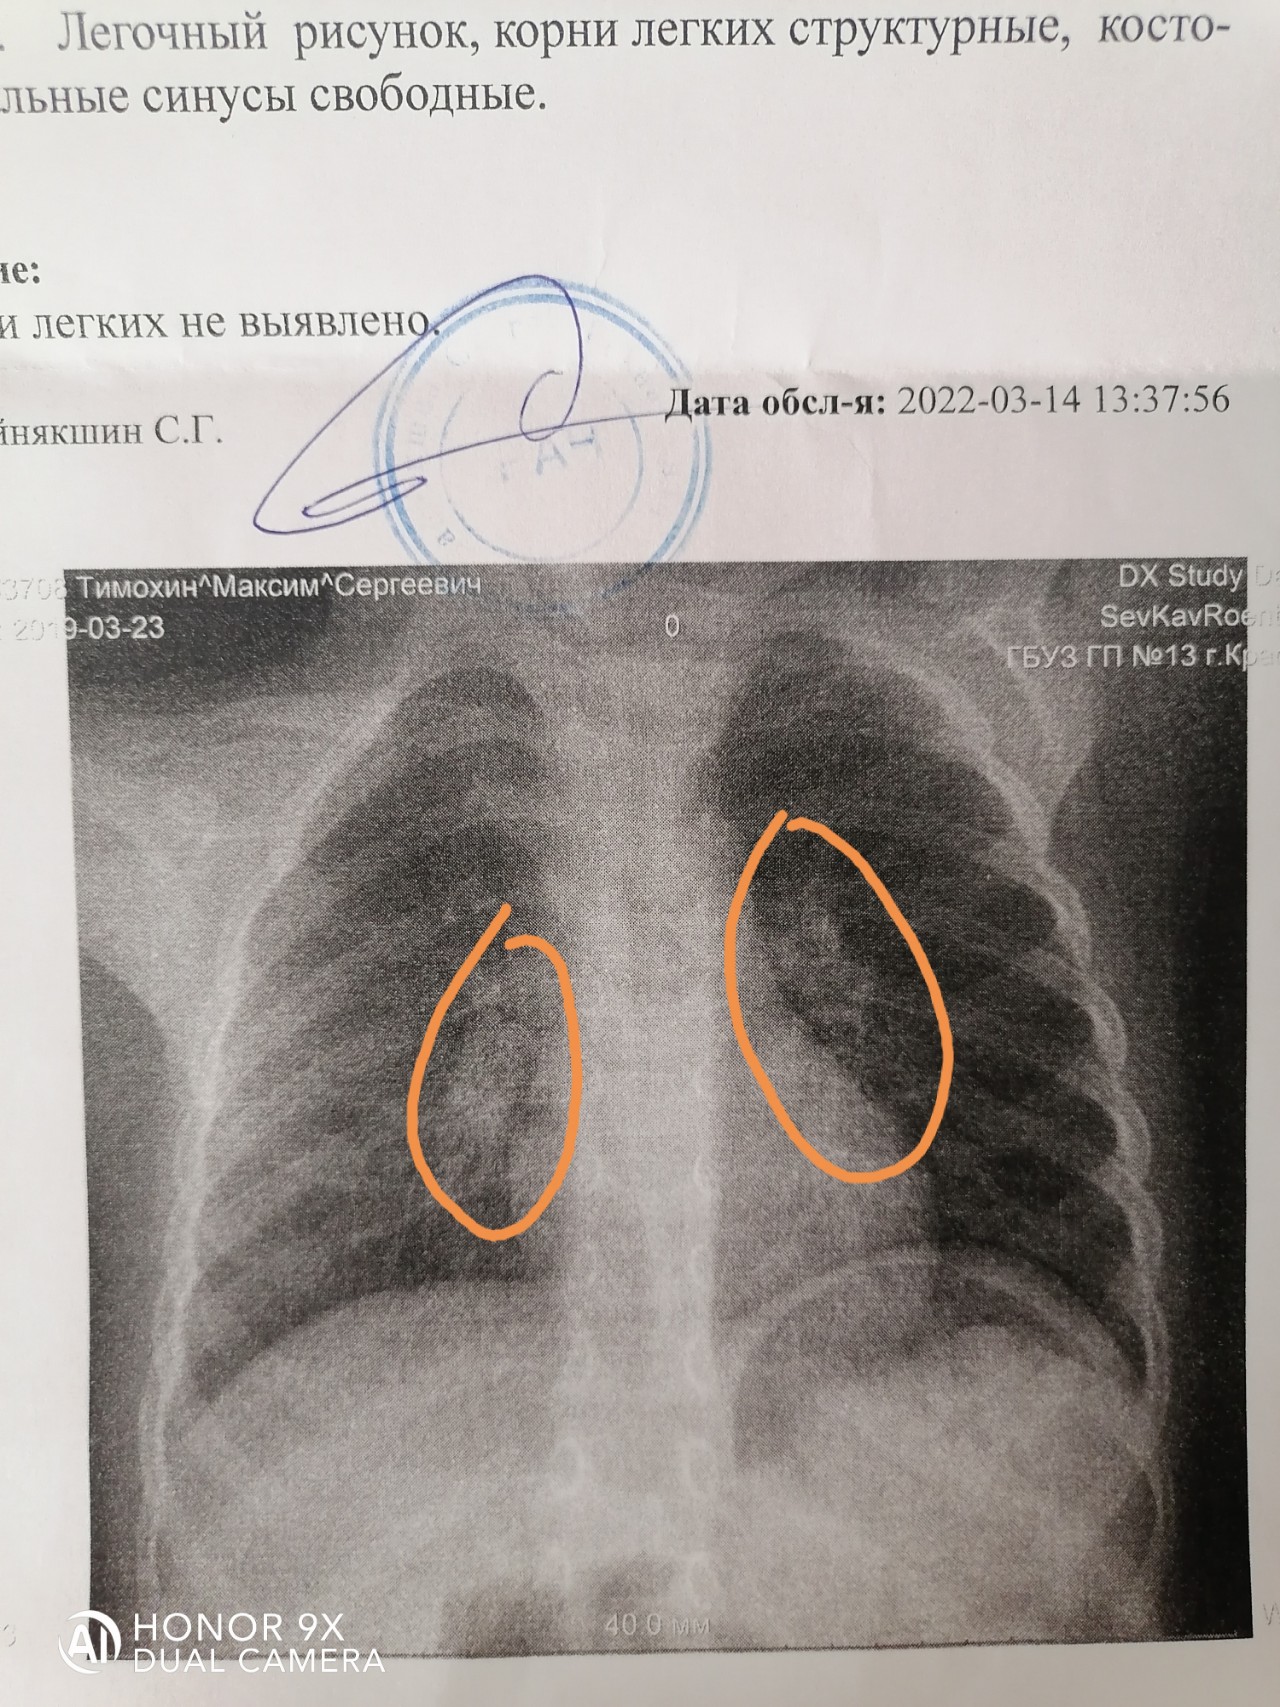

Фотографии, демонстрирующие обнаруженное усиление легочного рисунка

Раздел: Фотодневник открытий